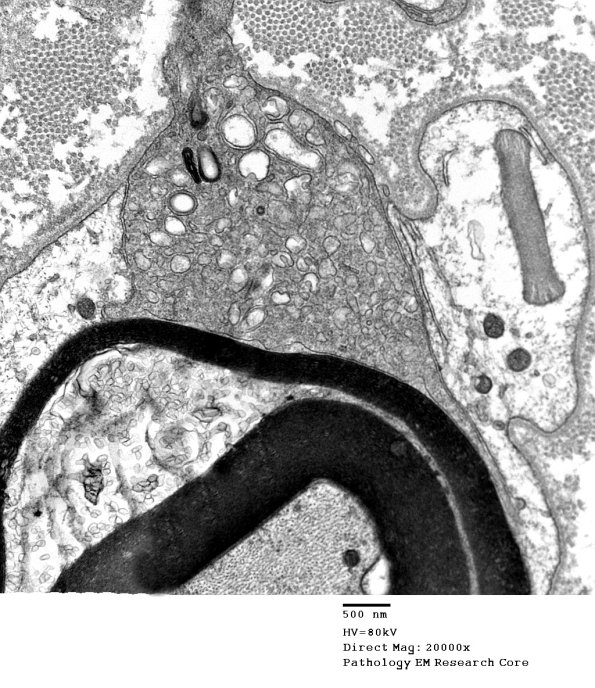

This macrophage has entered and displaced the Schwann cell and begun to peel off strips of myelin. (electron micrographs)